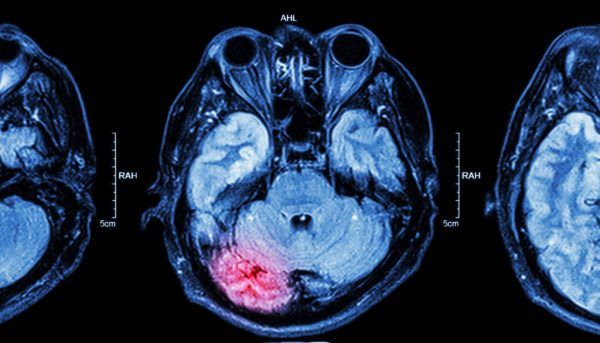

Артерийн даралт ихсэх өвчний гол хүндрэл бол тархинд цус харвах эмгэг (цус харвалт) юм. Дэлхийн улс орнуудаас уг эмгэгээр МОНГОЛ УЛС 1 байранд ордог.

Артерийн даралт ихсэх бол цус харвалтын хамгийн том эрсдэлт хүчин зүйл, хэрвээ та цусны даралтаа хянаж чадахгүй бол цус харвалт үүсэх эрсдэл 2-4 дахин ихсэнэ. Доктор Н.Рост тархинд цус харвах эмгэгийн хамгийн том эрсдэлт хүчин зүйл бол артерийн даралт ихсэх эмгэг хэмээн зөвлөжээ. Иймд, артерийн даралтыг тогтвортой хянах, ихэсвэл эмчлэх нь маш чухал.